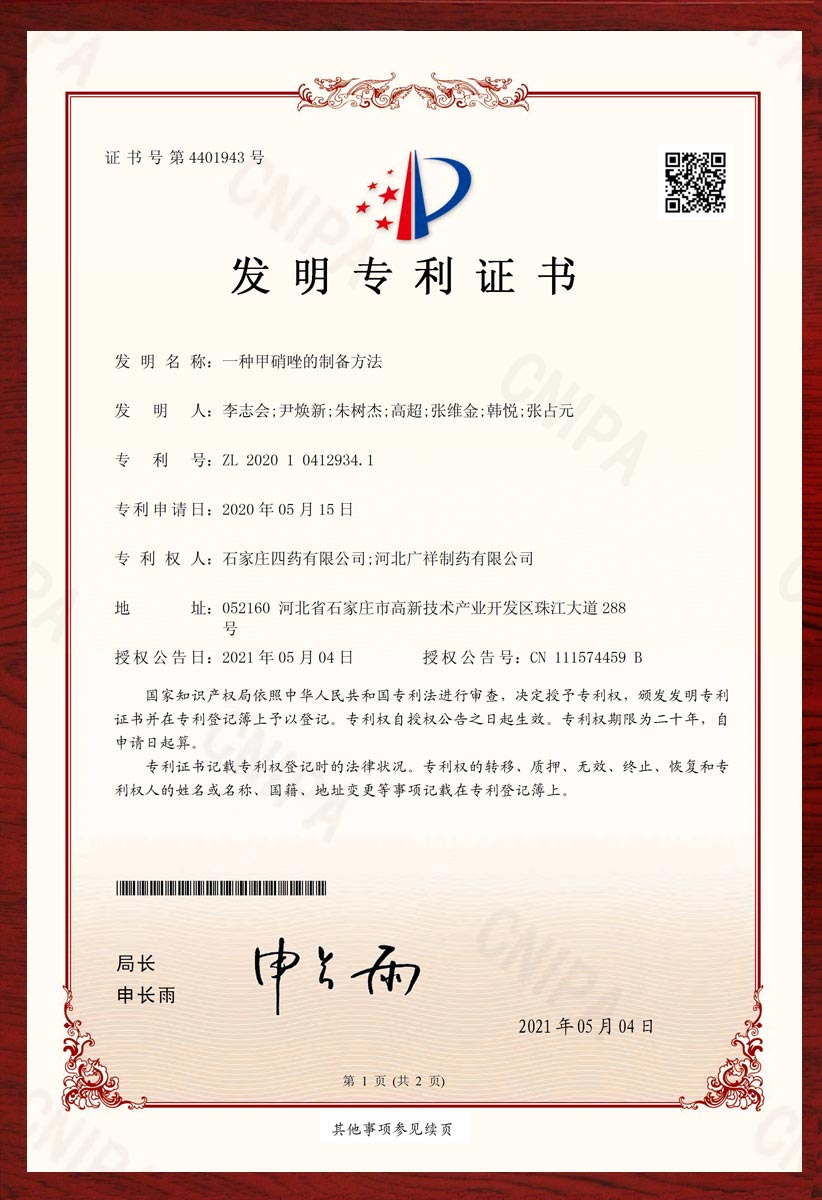

专利证书